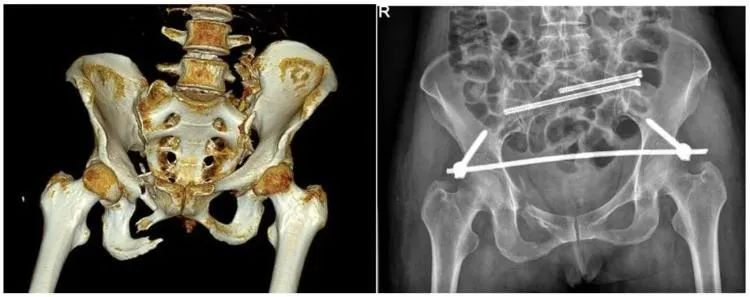

【醫療科普】:穩定性骨折影像

穩定性骨折

【醫療科普】:不穩定性骨折影像

不穩定性骨折

普愛醫療推出的大平板一體式C形臂PLX119C,配置30cm×30cm平板探測器,大視野,能夠呈現更多圖像細節,對于諸如骨盆雙側骨折類型手術或骨盆后環內固定術具有應用優勢,一次曝光可獲取全部骨折部位影像,可簡化曝光流程,提高手術效率。